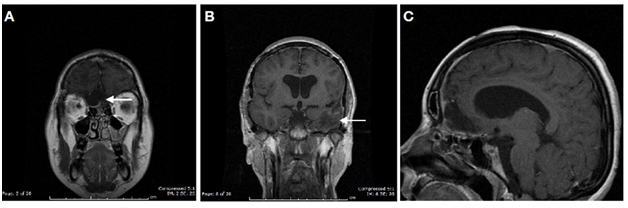

A Computed Tomography (CT) scans and brain magnetic resonance imaging (MRI) was performed and showed multiple intracranial meningiomas (Figure 1).

Figure 1 (A) Post-contrast MRI axial T1-weighted sequence shows giant olfatory groove meningioma and a giant left lesser wing meningioma. The tumoral masses are separated by a thin layer of brain parenchyma (black arrow). (B) T1 Gadoline enhanced sagittal MRI shows the olfatory groove meningioma. Hyperintense to grey matter and extends anteriorly along the anterior cranial fossa floor. (C,D) T1 Gadoline enhanced coronal MRI illustrates the important mass effect on the anterior and medium skull base, secondary to giant meningiomas and the brain herniation. C: The tumor cause the collapse and superior displacement of the left temporal horn (black arrow).

A giant meningioma of the right olfactory groove measuring 7cm x 6cm x 5.2cm (Figure 1); a left giant lesser sphenoid wing meningioma measuring 7cm x 6.5cm x 4.8cm (Figure 2); both tumors producing significant edema and brain herniation (Figures 1&2). Small bilateral vestibular schwannomas, two small falx meningiomas and a cervical schwannoma from C1 to C3 (Figure 3).